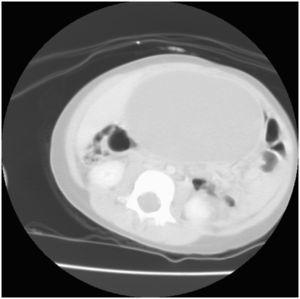

Se realiza radiografía abdominal mediante la que se observa una imagen homogénea densidad agua, con efecto de masa inframesocólica sin calcificaciones. En la ecografía abdominal se observa una masa de 20cm de diámetro de contenido líquido y con zonas hiperecoicas móviles con densidad grasa, sin poder establecer organodependencia. La tomografía computarizada (TC) abdominopélvica con contraste muestra una masa abdominal bien delimitada de predominio densidad líquido, tabicada en su polo craneal; el diagnóstico de sospecha es de quiste mesentérico (figura 1). Se realiza una gammagrafía con metayodobencilguanidina, en la que se hallaba un área de hipocaptación redondeada de localización abdominal, una gammagrafía ósea y una serie de marcadores tumorales normales.

Figura 1. Tomografía computarizada abdominal: masa abdominal homogénea bien delimitada de predominio densidad líquido.